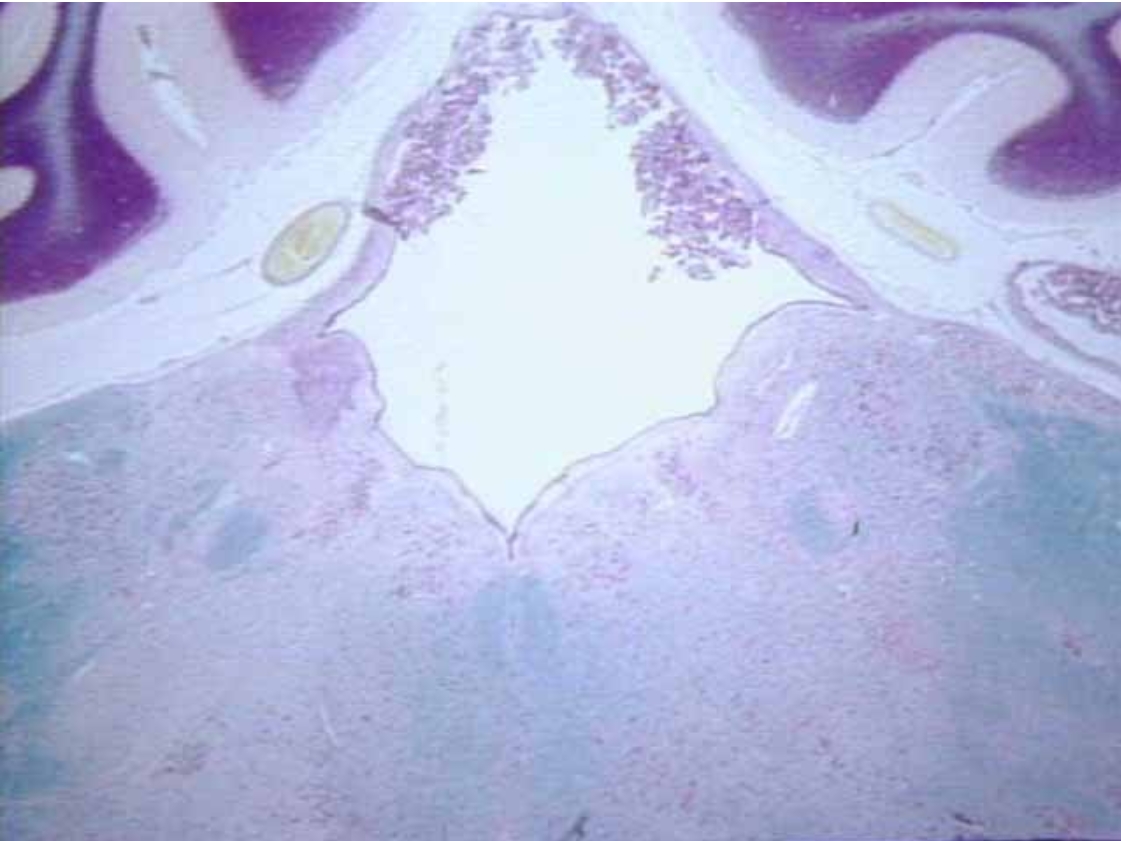

What is this

Midsagittal section of cerebellum (Microscopic real view)